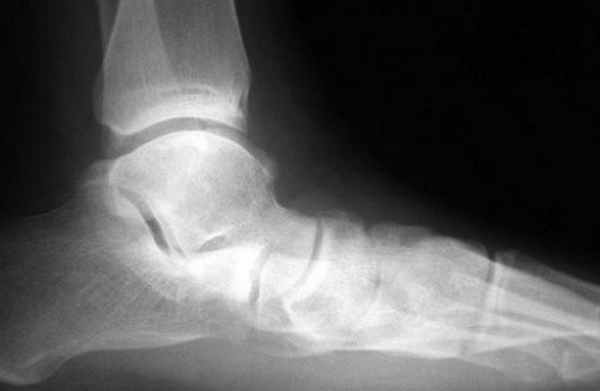

В первую очередь показано выполнение рентгенографии с нагрузкой в прямой и боковой проекции. При этом в прямой проекции выявляется неполное покрытие суставной поверхности головки таранной кости ладьевидной костью, увеличенный угол между таранной костью и первой плюсневой костью (угол Simmon), что встречается со 2 А стадии.

На боковых рентгенограммах определяется увеличенный таранно-плюсневый угол (угол Meary >4° свидетельствует о плоской стопе). Также снижается угол высоты пяточной кости (в норме 17-32°).

На 3-4 стадиях определяются признаки подтаранного артрита, на 4 стадии появляется картина подвывиха таранной кости в голеностопном суставе.